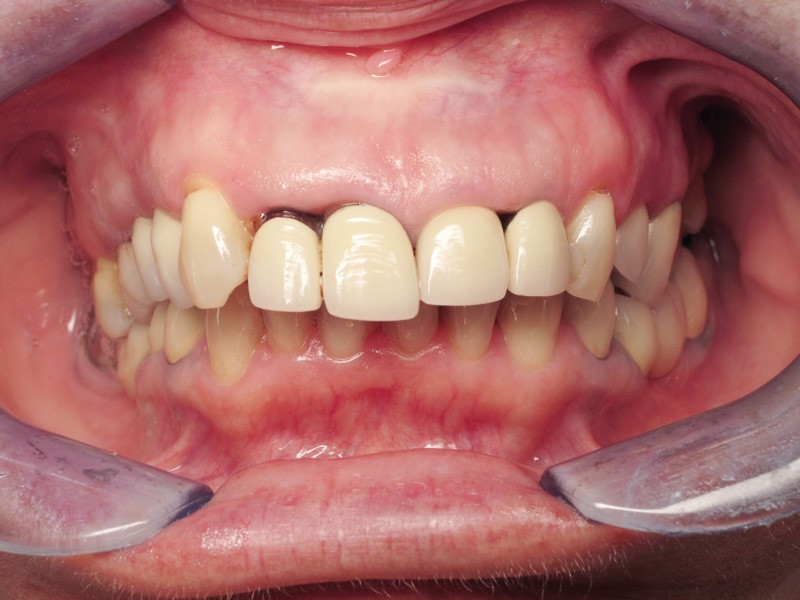

Madame J., âgée de 63 ans, consulte pour des douleurs chroniques localisées au niveau de 14 et de 21. L’examen endobuccal révèle la présence de prothèses anciennes, de soins conservateurs et d’un implant posé depuis 4 ans. On note une inflammation généralisée du parodonte superficiel avec présence de plaque et de tartre et une mobilité de certaines dents dont les incisives maxillaires droites. Dès ce stade, le surguidage antérieur du couple 11/12, reconstitué par des couronnes solidarisées, est à mettre en relation avec la souffrance parodontale observée (fig. 1).

Une inflammation de la zone péri-implantaire (24), en relation avec le motif de la consultation est également visible dès ce premier examen.